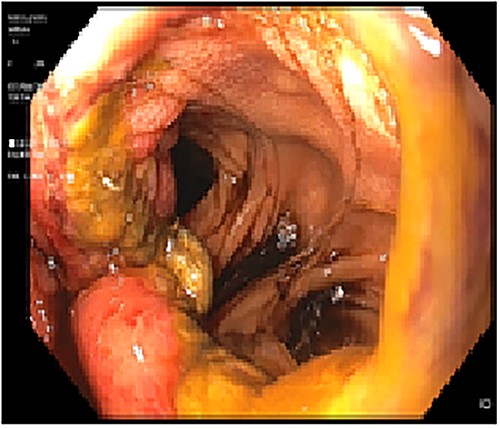

The patient was referred for laparoscopic revision surgery with conversion to RYGB (Fig. 3). In the postoperative period, a torpid evolution included vomiting on various occasions, as well as the detection of ascaris on one occasion. A new upper GI endoscopy showed evidence of permeable gastrojejunal anastomosis and acute inflammatory changes (Fig. 4), and the patient received antiparasitic treatment. Because of persistent symptoms of obstruction, a new surgical intervention was performed, which showed the presence of ascaris in the entero-enteric anastomosis causing its obstruction (Fig. 5). A new anastomosis was performed at a distance of 30 cm from the obstruction (Fig. 6). After the patient showed improvement and tolerated a liquid diet, she received treatment for ascaris and was discharged with good evolution.

Acute inflammatory changes associated with gastrojejunal anastomosis.